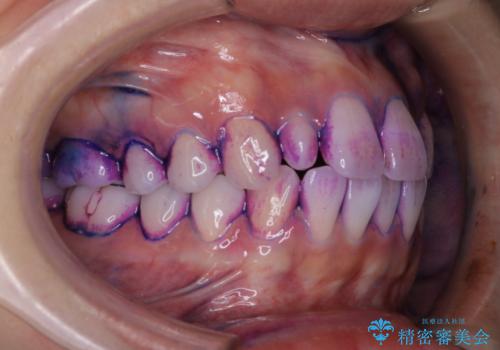

ステインが全体的についていたのでPMTCでステインを除去しオフィスホワイトニングを行いました。

ホワイトニングは薬剤を塗布し、レーザー照射を三回行いました。